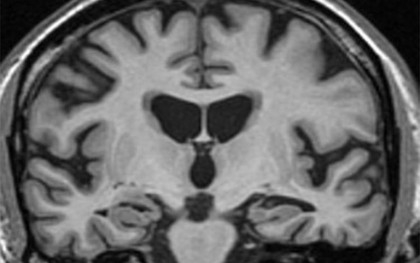

Pentru studiu, cercetătorii au utilizat un model de învățare automată bazat pe RMN pentru estimarea vârstei creierului, pe care l-au aplicat asupra participanților la un studiu de cercetare anterior. Persoanele incluse în studiu, cu vârsta cuprinsă între 69 și 72 de ani, au fost urmărite pentru toată viața. Vârstele estimate ale creierului participanților au variat între 46 și 93 de ani, la momentul primei estimări. Revizuirea unor factori de risc apăruți pe parcursul vieții le-a permis cercetătorilor să explice aproape o treime din variabilitatea vârstei creierului.

Rezultatele analizelor au arătat că o proastă sănătate la vârstele de 36 sau 69 de ani este asociată cu o sănătate cerebrală proastă și o vârstă a creierului peste cea a individului. Studiul actual vine în completarea unui studiu anterior, care a demonstrat faptul că persoanele cu hipertensiune arterială la vârsta de 36 de ani vor avea o mai proastă sănătate cerebrală de-a lungul vieții. Studiul nu a găsit asocieri între funcția cognitivă în copilărie, nivelul de educație sau statutul socioeconomic și un creier îmbătrânit prematur.

Studiul arată, de asemenea, că barbații tind să se confrunte mai frecvent cu îmbătrânirea prematură a creierului și că vârsta mai înaintată a creierului decât vârsta reală a unui individ este asociată cu o concentrație mai mare de proteină ușoară de neurofilament (NFL) în sânge. În prezent, valorule NFL sunt tot mai frecvent considerate un marker al degenerării neurologice.